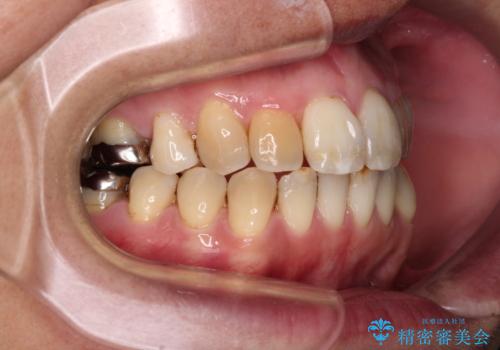

前歯の後戻り インビザラインでの再矯正治療

- かつて抜歯矯正を行ったものの、後戻りをしてしまったとのことで来院された患者様です。

上顎前歯が前突し、隣の歯が裏側に移動してきている状態でした。

飲み込みの状態を確認したところ、舌の突出癖が認められたため、それによる後戻りの可能性が高いと考え、舌のトレーニングを指導しました。

舌のトレーニングをしっかりと行ってくださり、10ヶ月で希望通りの歯列となりました。

日頃から飲まれる飲み物の影響で着色しやすいため、来院の度に着色除去のクリーニングも行っていました。